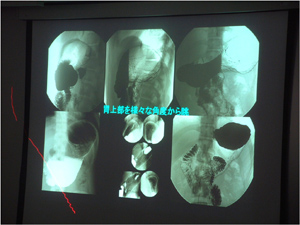

プログラム3 特別講演

8月例会において特別講演が執り行われました.講師は元会長本田幹雄先生でした.現在NPOで推奨されている基準撮影法から追加撮影へどうつなぐのか,また,盲点となりやすい部位を知り,ルーチン撮影にどう活かすのか,圧迫できない部位は二重造影像が主体となるので,どういうふうに撮影するのかなど,多くの症例写真を提示していただきわかりやすく説明して頂きました.ほんとうにありがとうございました.